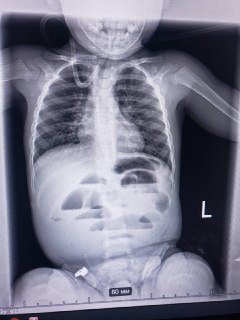

Лікарі Дніпра врятували дитину, яка проковтнула гідрогелеву кульку До Регіонального медичного центру родинного здоров’я...